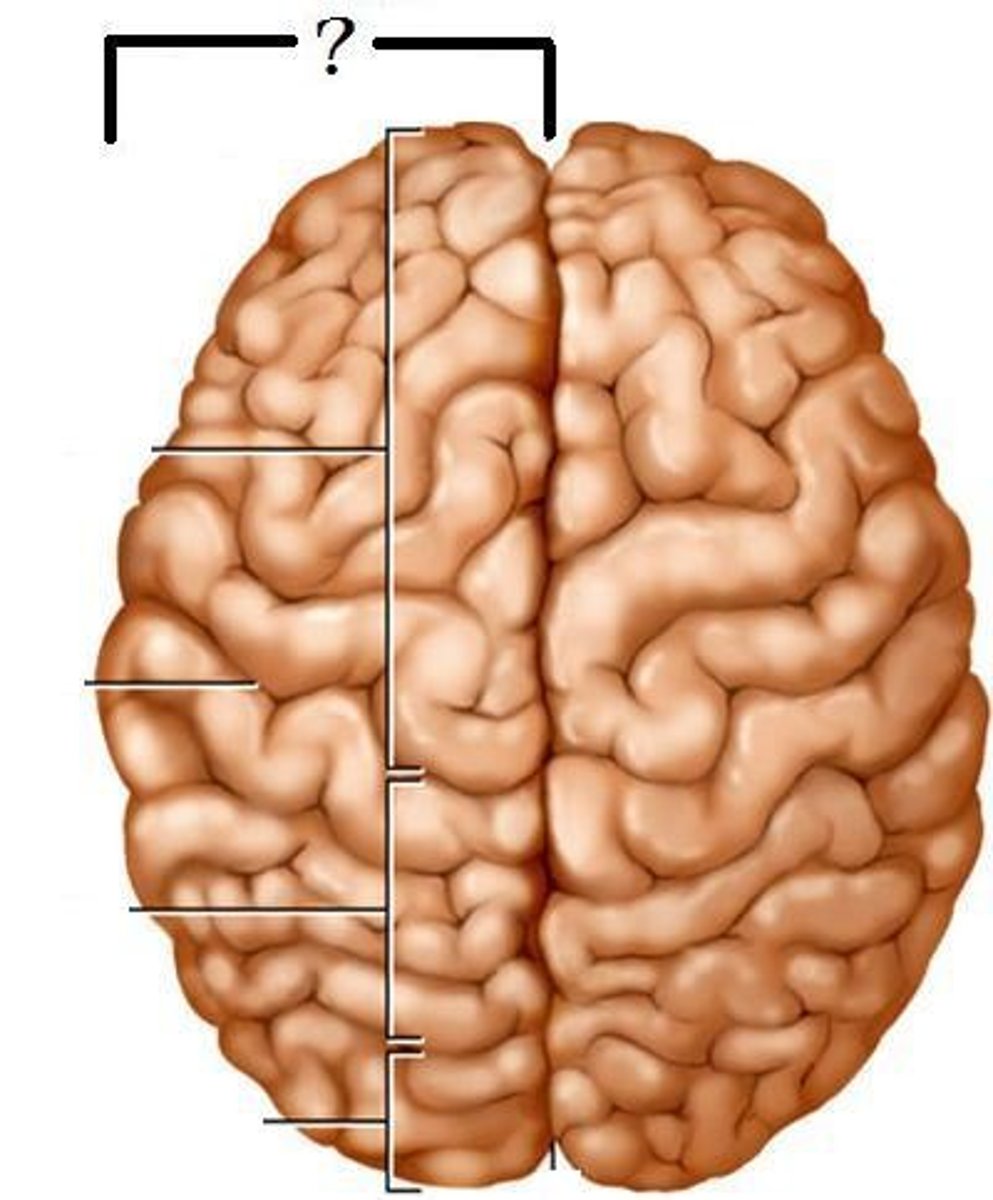

longitudinal fissure

separates cerebral hemispheres

left hemisphere

controls language, math, and logic

right hemisphere

controls perception of physical environment, art, nonverbal communication, music, etc.

central sulcus

precentral gyrus

frontal lobe

lateral sulcus

post central gyrus

pareital lobe

occipital lobe

transverse fissure

separates cerebrum from cerebellum

temporal lobe